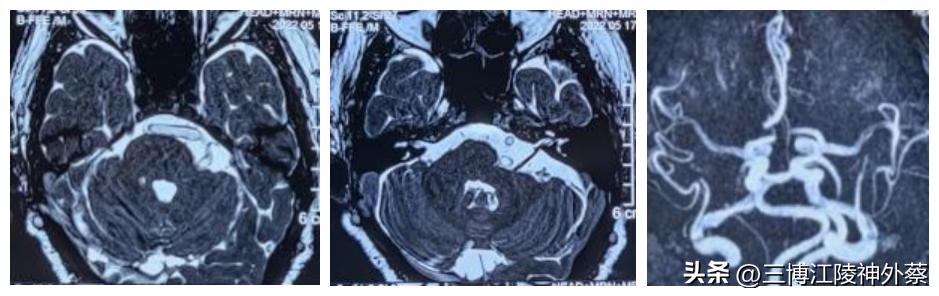

辅助检查MRI提示:椎基底动脉左偏;基底动脉与左侧三叉神经及面神经关系密切,似有骑跨。

(如图所示:可见明显左偏增粗的椎基底动脉与左侧三叉神经及面神经关系密切)